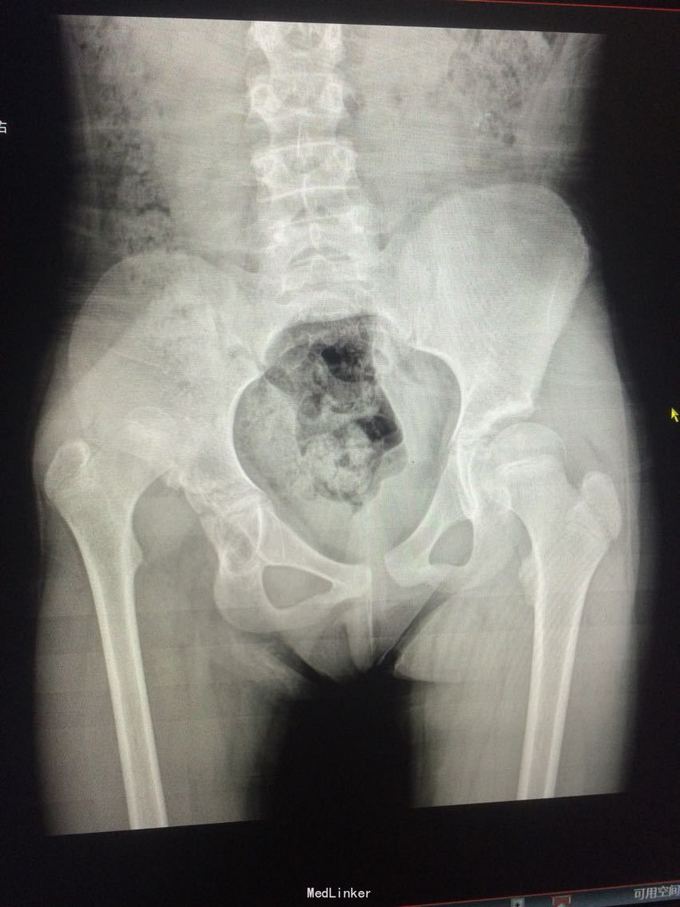

患者11岁,手术治疗效果怎么样

自幼左髋关节脱位